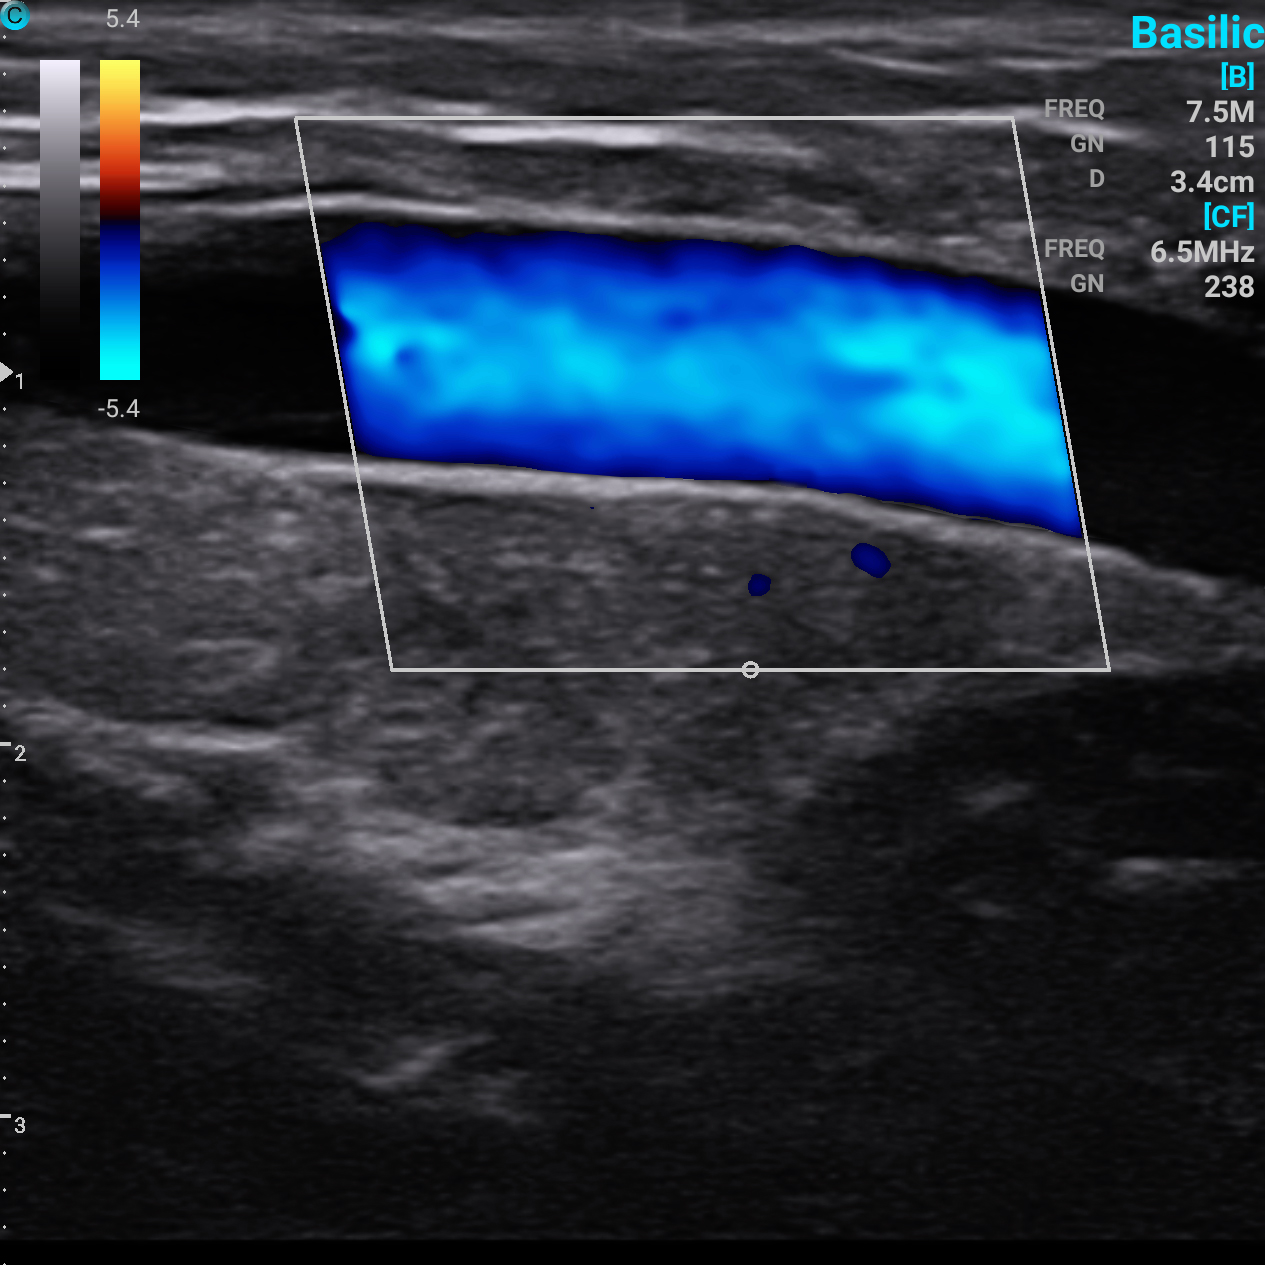

贵要静脉 B模式